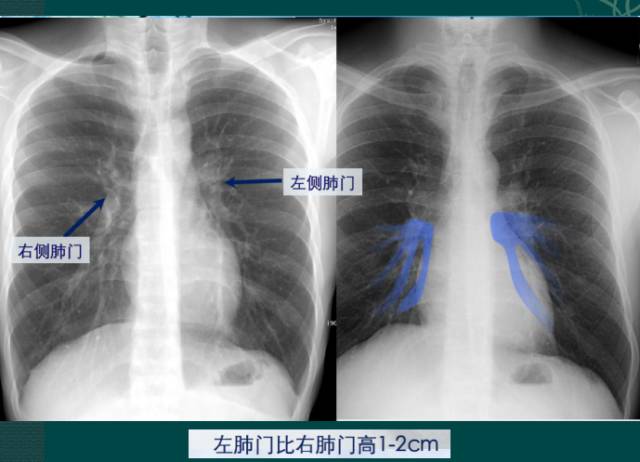

4.肺门的大小和位置

x线肺门指肺动脉、肺叶动脉、肺段动脉、伴行支气管以及肺静脉构成。

右肺门可分为上、下两部。上部约占1/3,由上肺静脉、上肺动脉及下肺动脉后回归支构成。上肺静脉下后干构成右上肺门的外缘;右肺门下部 约占2/3,由右下肺动脉干构成,其正常宽度不超过15mm,沿中间段支气管外缘平行向外下走行。右肺门上、下部相交形成一钝的夹角,称肺门角,正常该角顶清晰。如下图

左肺门亦分为上、下两部。上部由左肺动脉及其分支、左上叶支气管和左上肺静脉及其分支构成;下部由左下肺动脉及其分支构成,常被心影所遮盖。